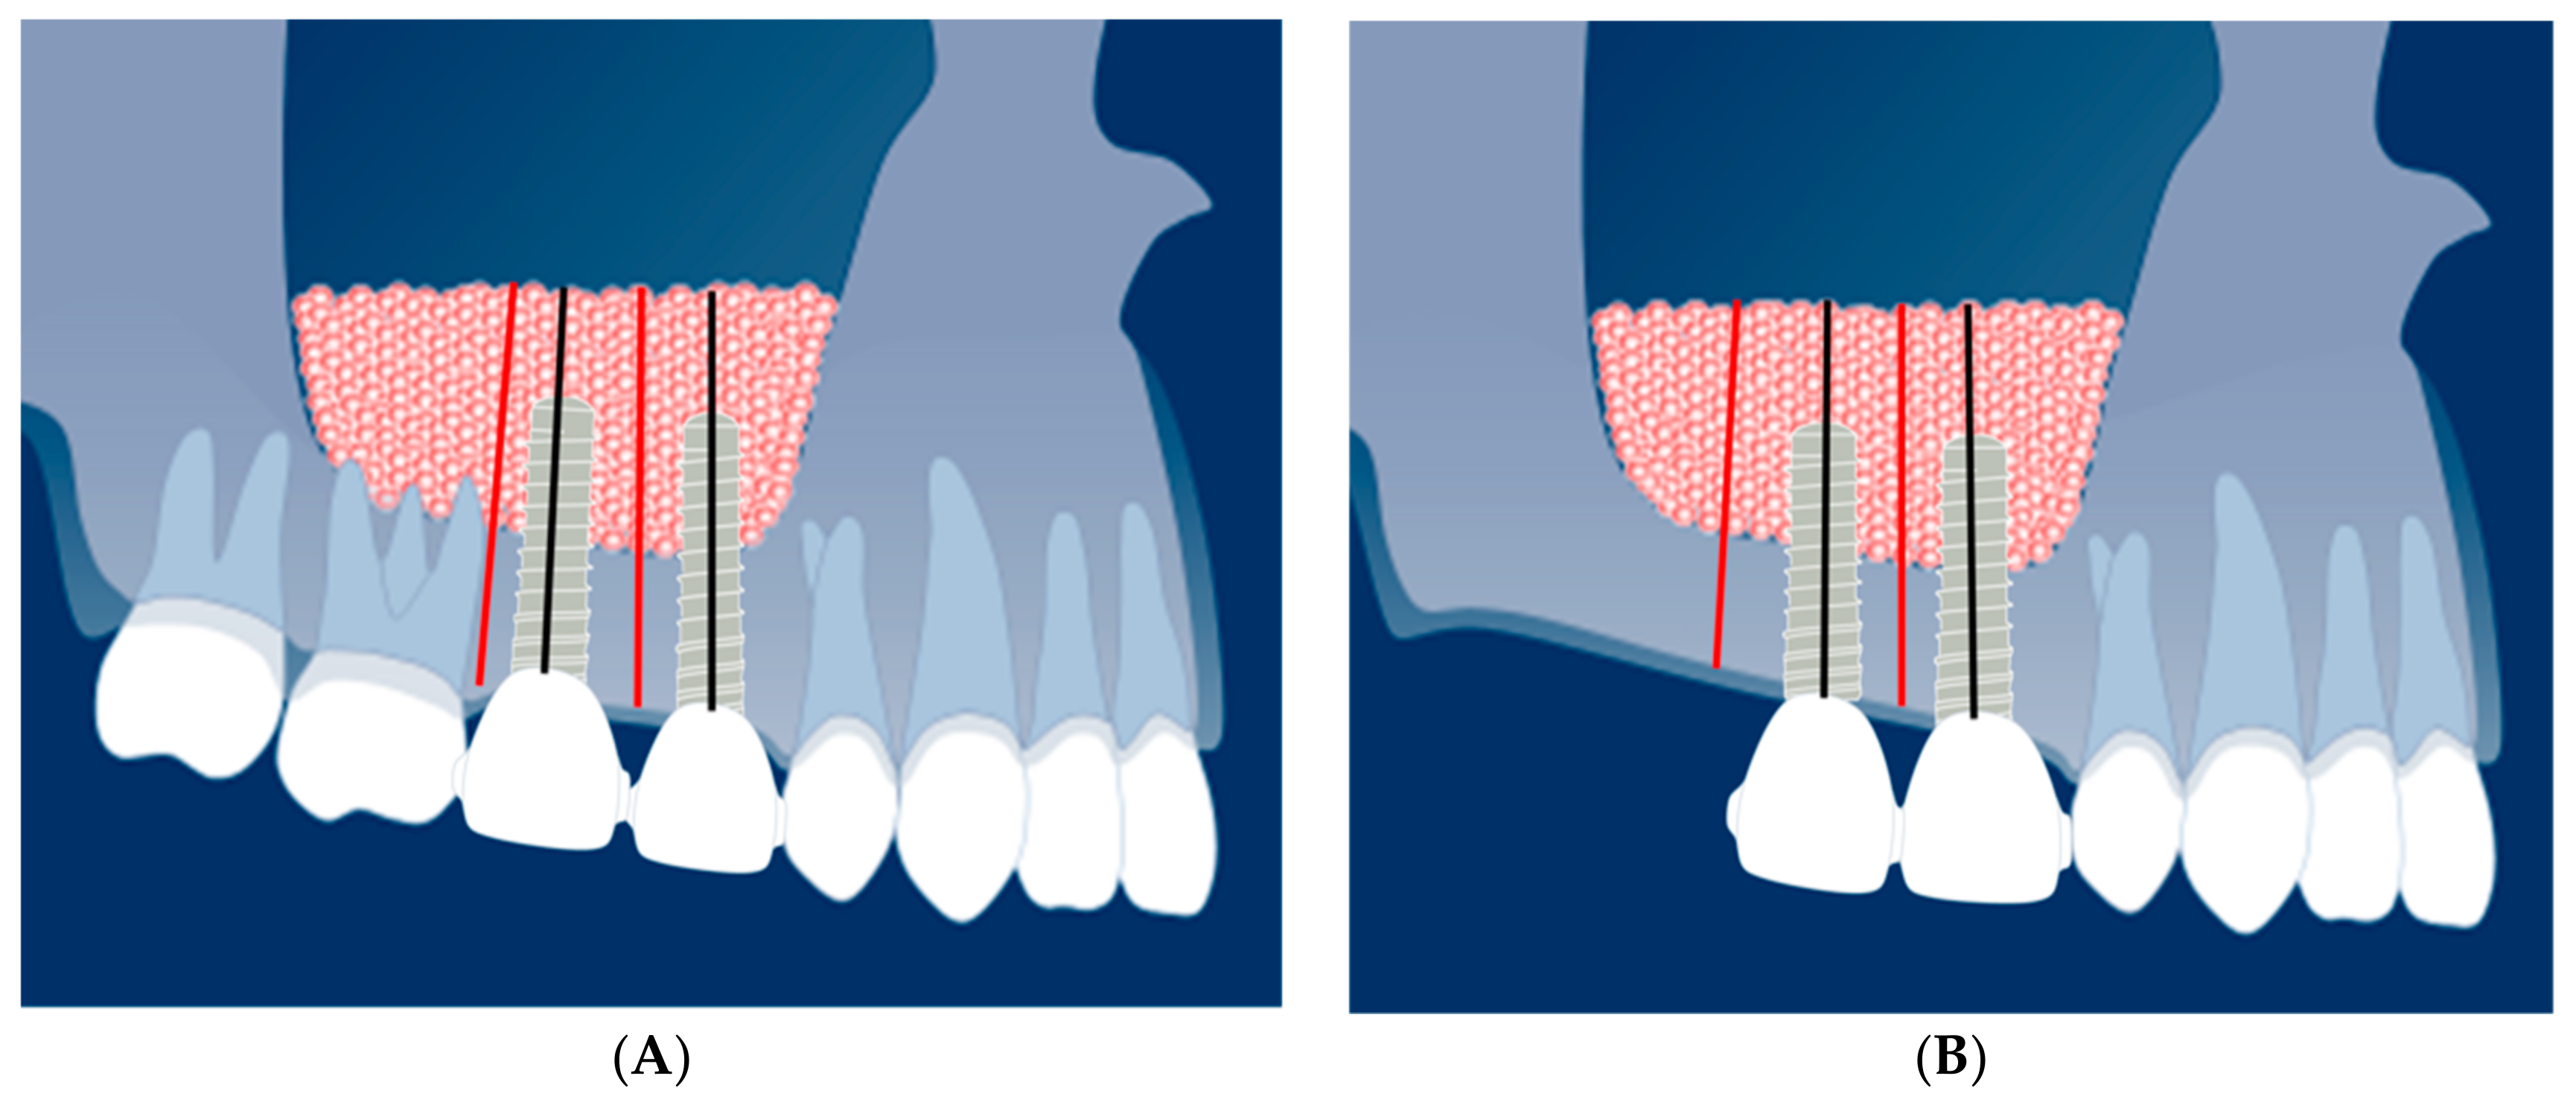

2.4. Radiological Evaluation